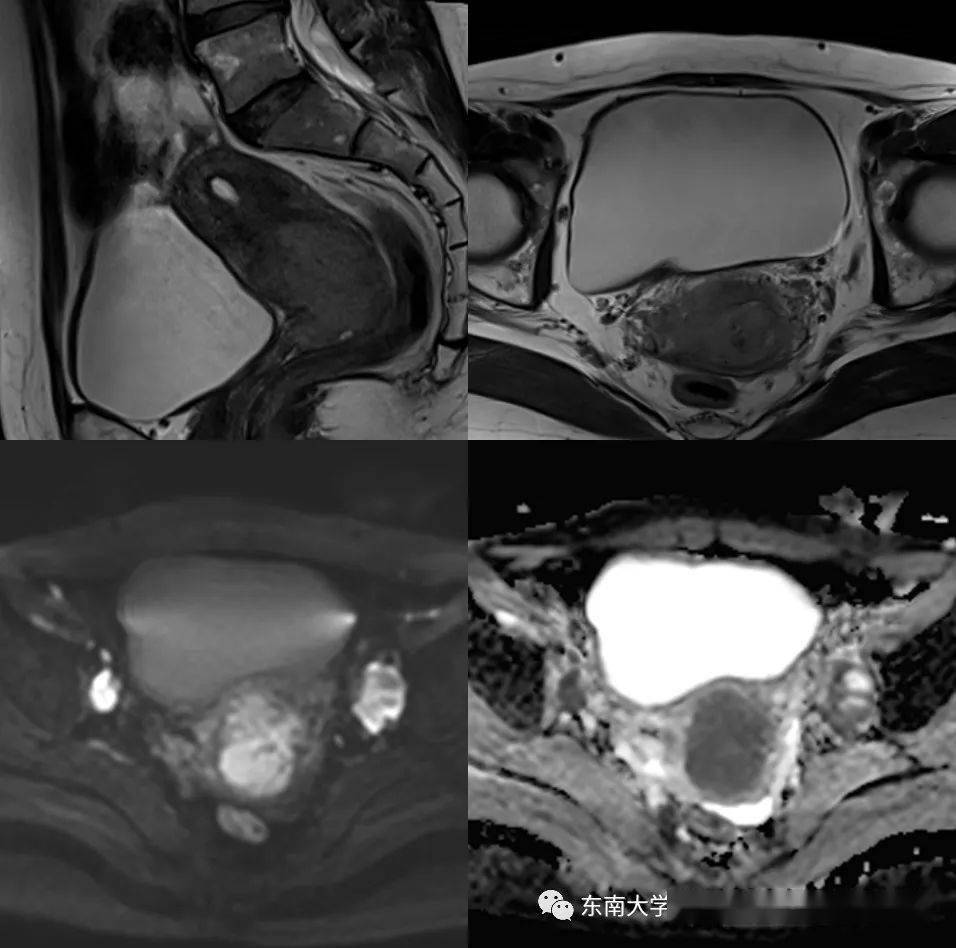

所有病患没有阴道镜检查和子宫切除、子宫颈上皮内瘤 样病变既往史。 1.2 方法 在检查操作前24h 受检者应禁止性生活,不可进行阴道冲洗、用药、检查等 检查时取截石位,运用阴道窥器将宫颈做充分暴露,将宫颈分泌物擦拭干净, 对宫颈颜色、形态、血管等情况进行检查,在宫颈运用5%酸醋做涂抹,而后对 转化区、血管、上皮的变化做观察。对宫颈涂抹1%碘溶液进行碘试验,当柱状、 未成熟化生、角化、非典型等上皮出现碘不着色的情况为阴性表现,则需要进行 部位的活检,如果阴道镜检查没有发现异常,则进行3、6、9、12 点的活检。 1.3 评估观察 阴道镜的正常检查情况为图像为原始的柱状上皮、鳞状上皮和正常转化区情 况,异常情况则图像有镶嵌、白斑、點状血管、畸形血管、醋酸白色上皮或者碘阴 性表现。而后记录阴道镜检查和病理检查的病变与正常情况的人数,两者做对比 1.4 统计学分析 .将采集到的数据通过spss17.0 统计学软件做分析处理,计数资料运用卡方 来检验,以P<0.05 作为组间差异具有统计学意义的标准。 结果通过表1 可知,阴道镜下结果与病理活检的结果符合率较高,两组差异不明显;同时检出率年龄段主要集中在31-50 岁年龄段,其中41-50 发年龄段,子宫颈癌、子宫颈上皮内瘤变的比例均为最高。

表1:受检者者阴道镜检查结果与病理检查的比较 表2:阴道镜下活检病理结果与年龄的关系 讨论阴道镜可以对子宫颈表面进行微小病变的观察,替代肉眼无法识别的病变, 主要是对子宫颈结构、形态、颜色和碘反应做观察,例如异常血管、醋酸白色上 皮等。一般情况上显示为白色上皮情况较多,最具价值的图像以镶嵌异形血管、 点状血管等。而随着异常图像显示的情况和级别增高,病理结果的诊断中相关恶 性疾病的检出率也逐步提升。部分情况下炎症也会有阴道镜检验的异常图像出现 这种情况与对阴道镜显示图像上白色上皮的掌握程度欠缺,特别是非典型性的 增生和未成熟的上皮醋酸白色反应在一定程度上,形态上较难区分【2-3】。 在临床诊断上,不能仅仅依靠阴道镜的图像显示来对子宫颈病变做诊断, 需要根据病史、临床症状表现和病理学检验结果为准。阴道镜的检查结果准确性 与医生的视觉技术、经验等综合能力有关,对阴道镜的图像理解能力带有一定的 主观判断性,因此,在准确性上具有一定的失准可能性。因此,虽然阴道镜对子 宫颈病变的诊断具有一定重要作用,但是一定要结合病理检查结果进行综合评 估,这样才能保证诊断的准确性。 组织病理学检验是诊断子宫颈病变的金标准,阴道镜检查的结果主要依靠 病理结果来确定。

通过阴道镜对组织结构进行细微的观察,让活检定位更加精准 从而有效提僧活检的检出率和准确性,特别是子宫颈上皮内瘤变和早期浸润癌 的检出诊断具有关键作用。一般情况下,对于阴道镜下活检的采集,以多点活检 为主要方式,选择病变严重情况处。对于子宫颈管内的病变部位暴露困难,因此 误诊可能性高,运用子宫颈的扩张器检查可以有效的降低其误诊和漏诊的几率。 阴道镜下活检需要对阴道镜的使用有全面深入的认识,熟练操作以及提升对其 图像的了解,可以有效的发挥其阴道镜下活检的精准度。 本研究中,阴道镜下结果与病理活检的结果符合率较高,大部分在95%以 上的符合率,两组检出率的结果差异不明显;同时检出率年龄段主要集中在31- 50 岁年龄段,其中41-50 岁为高发年龄段,子宫颈癌、子宫颈上皮内瘤变的比例 均为最高。可以说明阴道镜检查结果与其活检配合可以有效的提升诊断的准确性 .适用于临床子宫颈病变的诊断运用,其中还要注意子宫颈病变与年龄的密切关 系,因此在高发年龄段要做好深入检查。 参考文献: [1]强萍,陈丽娟,陈萍.宫颈液基细胞学联合阴道镜下活检对子宫颈病变的 诊断价值[J].中国妇幼保健,2013(1): 172-173 [2]刘颖.TCT、HC2 及阴道镜检查在子宫颈病变检测中的应用[D].天津医科 大学,2014 [3]王春颖.宫颈液基细胞学联合阴道镜检查在宫颈病变诊断中的应用[D].大 连医科大学,2014